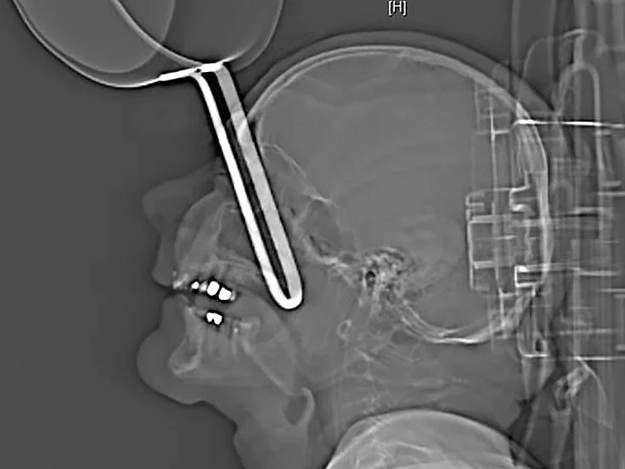

ALMANYA'da yaşanan olayın bir benzerine daha önce rastlamadınız. İsmi açıklanmayan 64 yaşındaki adamın hastanede çekilen röntgen filmi olayı aslında gayet açık gösteriyor. Evinin mutfağına sarhoş geldikten sonra, düşen ve tencere sapıyla birlikte yüzüne saplanan adam mucize bir şekilde acil servisi kendisi aradı.

Dr Carla Sander'in başında bulunduğu tıbbi ekip, adamın kafatasının röntgenini çekti ve acil müdahalede bulundu. Doktor Sander bulguları şöyle açıklıyor; "Tencere sapı kafatasının içine 10 cm kadar saplanmış, üst kısımdan gelerek orbitanın önündeki açıklığı delerek içeri girmişti."

Doktorlar adamın oldukça şanslı olduğunu düşünüyor. Çünkü tencere göz boşluğunun altından girip ne göze ne de beyine zarar vermedi. Daha sonra cerrahi operasyonlarla yaşlı adam eski sağlığına kavuştu.